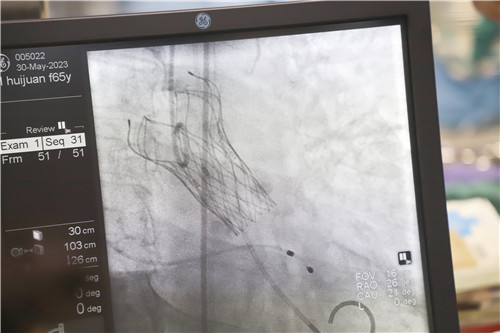

為保證創(chuàng)傷小、恢復(fù)快、并發(fā)癥可控,心血管內(nèi)科聯(lián)合麻醉科、醫(yī)學(xué)影像科、超聲醫(yī)學(xué)科等多學(xué)科會診,反復(fù)溝通討論,最終決定施行TAVR手術(shù),并征得王女士及家人的同意。該項(xiàng)微創(chuàng)介入技術(shù)對術(shù)者的技能操作水平和醫(yī)院的綜合救治能力要求極高,從大腿股動脈置入導(dǎo)管,再通過導(dǎo)管將人工生物心臟瓣膜輸送至已經(jīng)病變狹窄的瓣膜位置,取代其瓣膜功能。

不為良相,便為良醫(yī)。石化醫(yī)院心血管內(nèi)科團(tuán)隊(duì)在汪念東副院長的帶領(lǐng)下和皖南醫(yī)學(xué)院弋磯山醫(yī)院湯圣興教授的指導(dǎo)下,術(shù)中利用豬尾管懸吊AL1導(dǎo)管增強(qiáng)同軸跟進(jìn),經(jīng)過多學(xué)科四個小時的緊張救治,最終建立軌道成功置換瓣膜。

王女士術(shù)前測壓力階差高達(dá)110mmHg,在置換瓣膜后,壓力階差恢復(fù)到5mmHg,且無瓣周漏,在麻醉蘇醒后恢復(fù)了自主心率和自主呼吸。